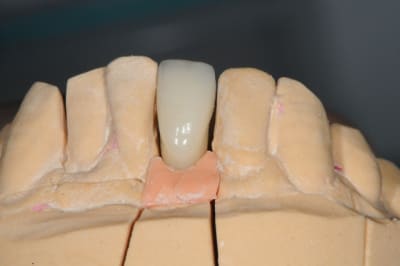

je me permet de ressusciter ce poste car j'ai placé la prothèse il y a un mois.

photo 4 +5: prise d'empreintes

photo 6-7-8-9: couronne finie.